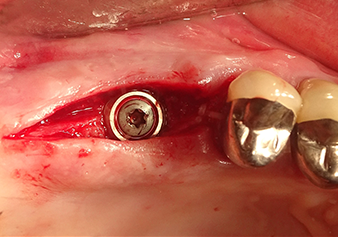

Après un contrôle intermédiaire (Fig. 4), une étape de préparation ultérieure est exécutée (Fig. 5). Puis on utilise l’insert Z35P hydraulique pour relever la membrane vers la position souhaitée (Fig. 6 et 7). Ensuite, une préparation piézochirurgicale supplémentaire est pratiquée sur le site implantaire, en utilisant pour terminer un burin rotatif et une fraise à épaulement jusqu’à 4,8 mm de diamètre d'implant. Avant l’insertion de l'implant, le matériau d’augmentation (taille de particules env. 0,8-1,6 mm) est introduit sous la membrane de Schneider (Fig. 8).

Implantation et restauration prothétique

Pour mettre en place le matériau d’augmentation en douceur en direction du sinus maxillaire, l’implant est inséré manuellement très lentement (Fig. 9). Pendant l’opération, la membrane est poussée de nouveau dans la direction crânienne. Au bout de deux mois, le site chirurgical cicatrise sans signes d’irritation. Six mois plus tard, la radio de contrôle révèle une augmentation significative de l'opacité indicative de l’ossification (Fig. 10). La restauration prothétique est réalisée avec une couronne métallo-céramique.